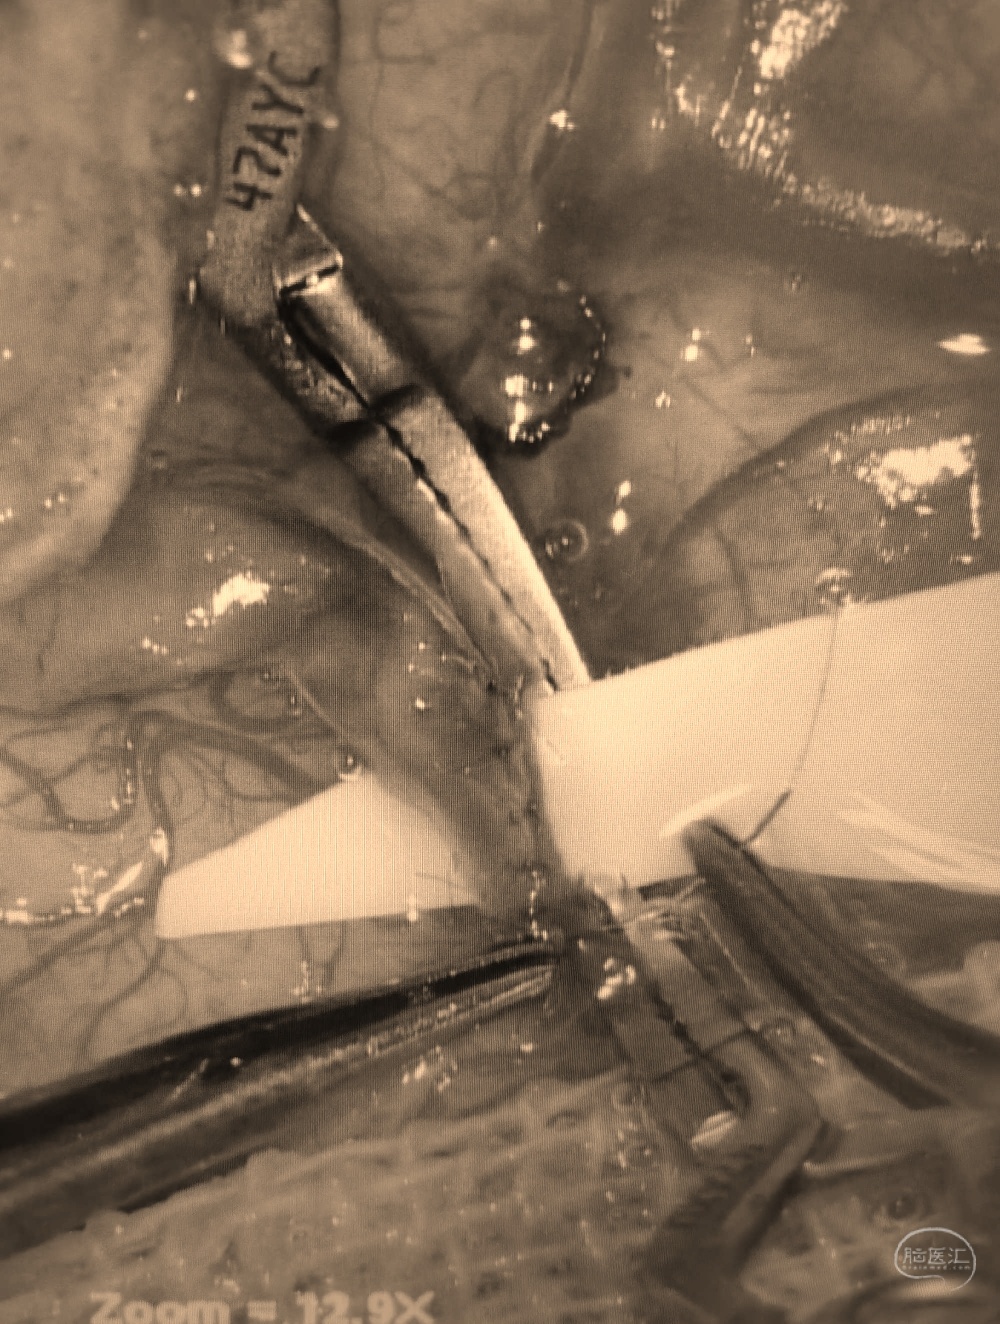

行颞浅动脉-M4端侧吻合。

吻合14针。

荧光造影示:吻合桥动脉通畅。

行颞浅动脉-M4端侧吻合。

颞浅A一只吻合,一只种植。吻合14针。

荧光造影示:吻合桥动脉通畅。

行颞浅动脉-M4端侧吻合。

吻合14针。

荧光造影示:吻合桥动脉通畅。

行颞浅动脉-M4端侧吻合。

吻合14针。

荧光造影示:吻合桥动脉通畅。

行颞浅动脉-M4端侧吻合。

吻合16针。

荧光造影示:吻合桥动脉通畅。